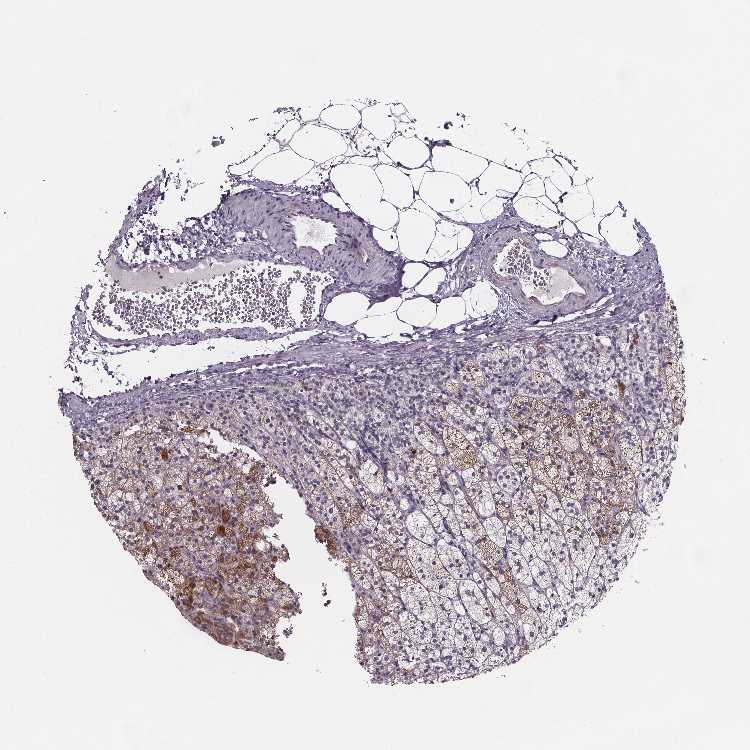

ADRENAL GLAND - Antibody stainingi

Antibody staining in the annotated cell types in the current human tissue is reported as not detected, low, medium, or high, based on conventional immunohistochemistry profiling in selected tissues. This score is based on the combination of the staining intensity and fraction of stained cells.

Each image is clickable and will lead to virtual microscopy that enables deeper exploration of all samples and also displays staining intensity scores, fraction scores and subcellular localization as well as patient and tissue information for each sample.

Antibody HPA028407Antibody HPA031642

Glandular cells Not detectedMedium